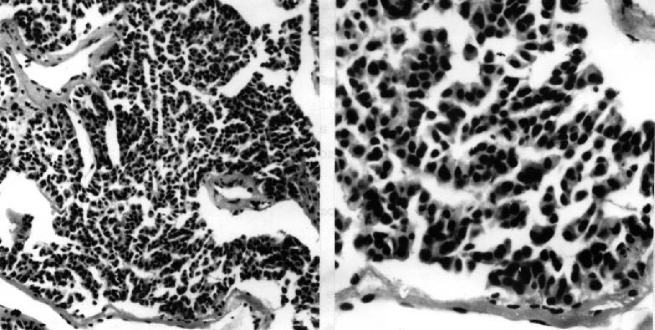

The introduction of the parameters was motivated by the fact that tumor cell shape (see Figures 6 and 7) represents a visual manifestation of an underlying balance of forces and chemical reactions [32]. Specifically, the parameters represent the following quantities:

The ability to estimate the growth pattern of an individual tumor cell type on the basis of morphological measurements should have general applicability in cellular investigations, cell–growth kinetics, cell transformation and morphogenesis [34].

Cell spreading alone is conducive to proliferation and increases in DNA synthesis, indicating that cell morphology is a critical determinant of cell function, at least in the presence of optimal growth factors and extracellular matrix (ECM) binding [35]. In many cells, the changes in morphology can stimulate cell proliferation through integrin-mediated signaling, indicating that cell shape may govern how individual cells will respond to chemical signals [36].

The proposed model (20)–(23) describes chaotic behavior relevant to the invasion of cancer cells (see Figures 5 and 6). As devices for controlling metastasis/chaos we suggest the following processes: Cellular retraining of cancer stem cells and/or activation of positive function of cyclin-dependent kinase inhibitor p27 and/or decreased expression of SATB1, which is correlated with aggressive tumor phenotype in breast cancer and shorter patient survival time [27, 29, 30, 31].